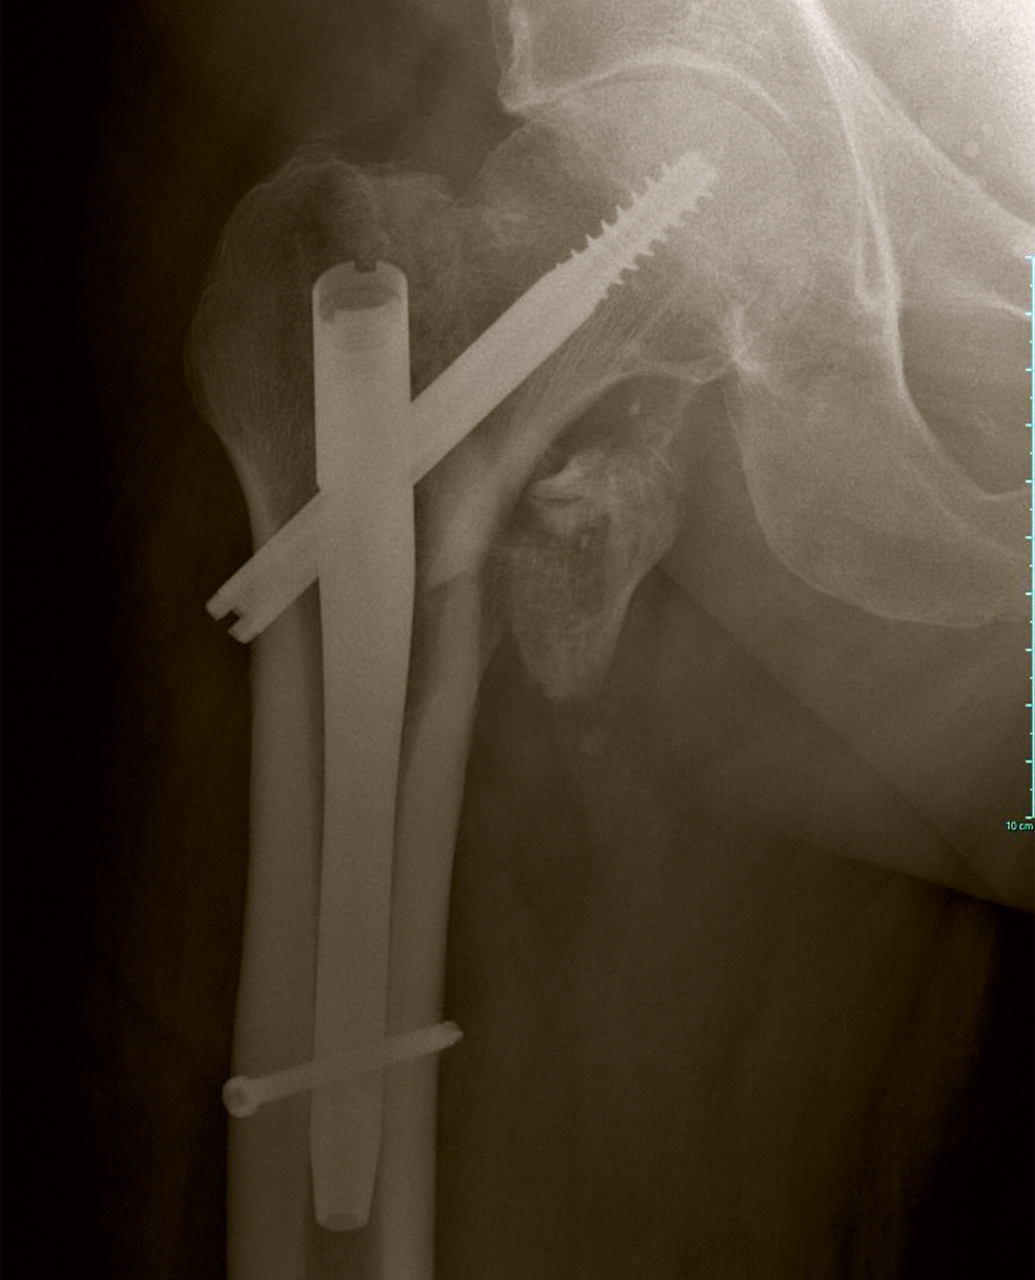

Voici la radiographie postopératoire.

Figure 3

Question 11 – De quel matériel s’agit-il ?

Question 12 – Quelles sont les complications possibles de ce type de fracture ?